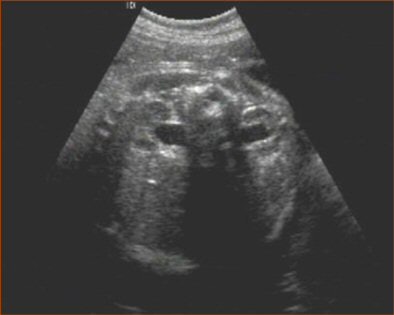

The third marker, mild renal pyelectasis, usually resolves after birth. About 2% to 3% of normal population are also likely to have pyelectasis. However, this is an important marker given that 17% to 25% of Down syndrome cases have hydronephrosis.

The kidneys are imaged in the transverse plane and measured in the anteroposterior plane. If the diameter is greater than 7 mm at 30-40 weeks, there is an increased risk of Down syndrome.

| Renal pyelectasis. |